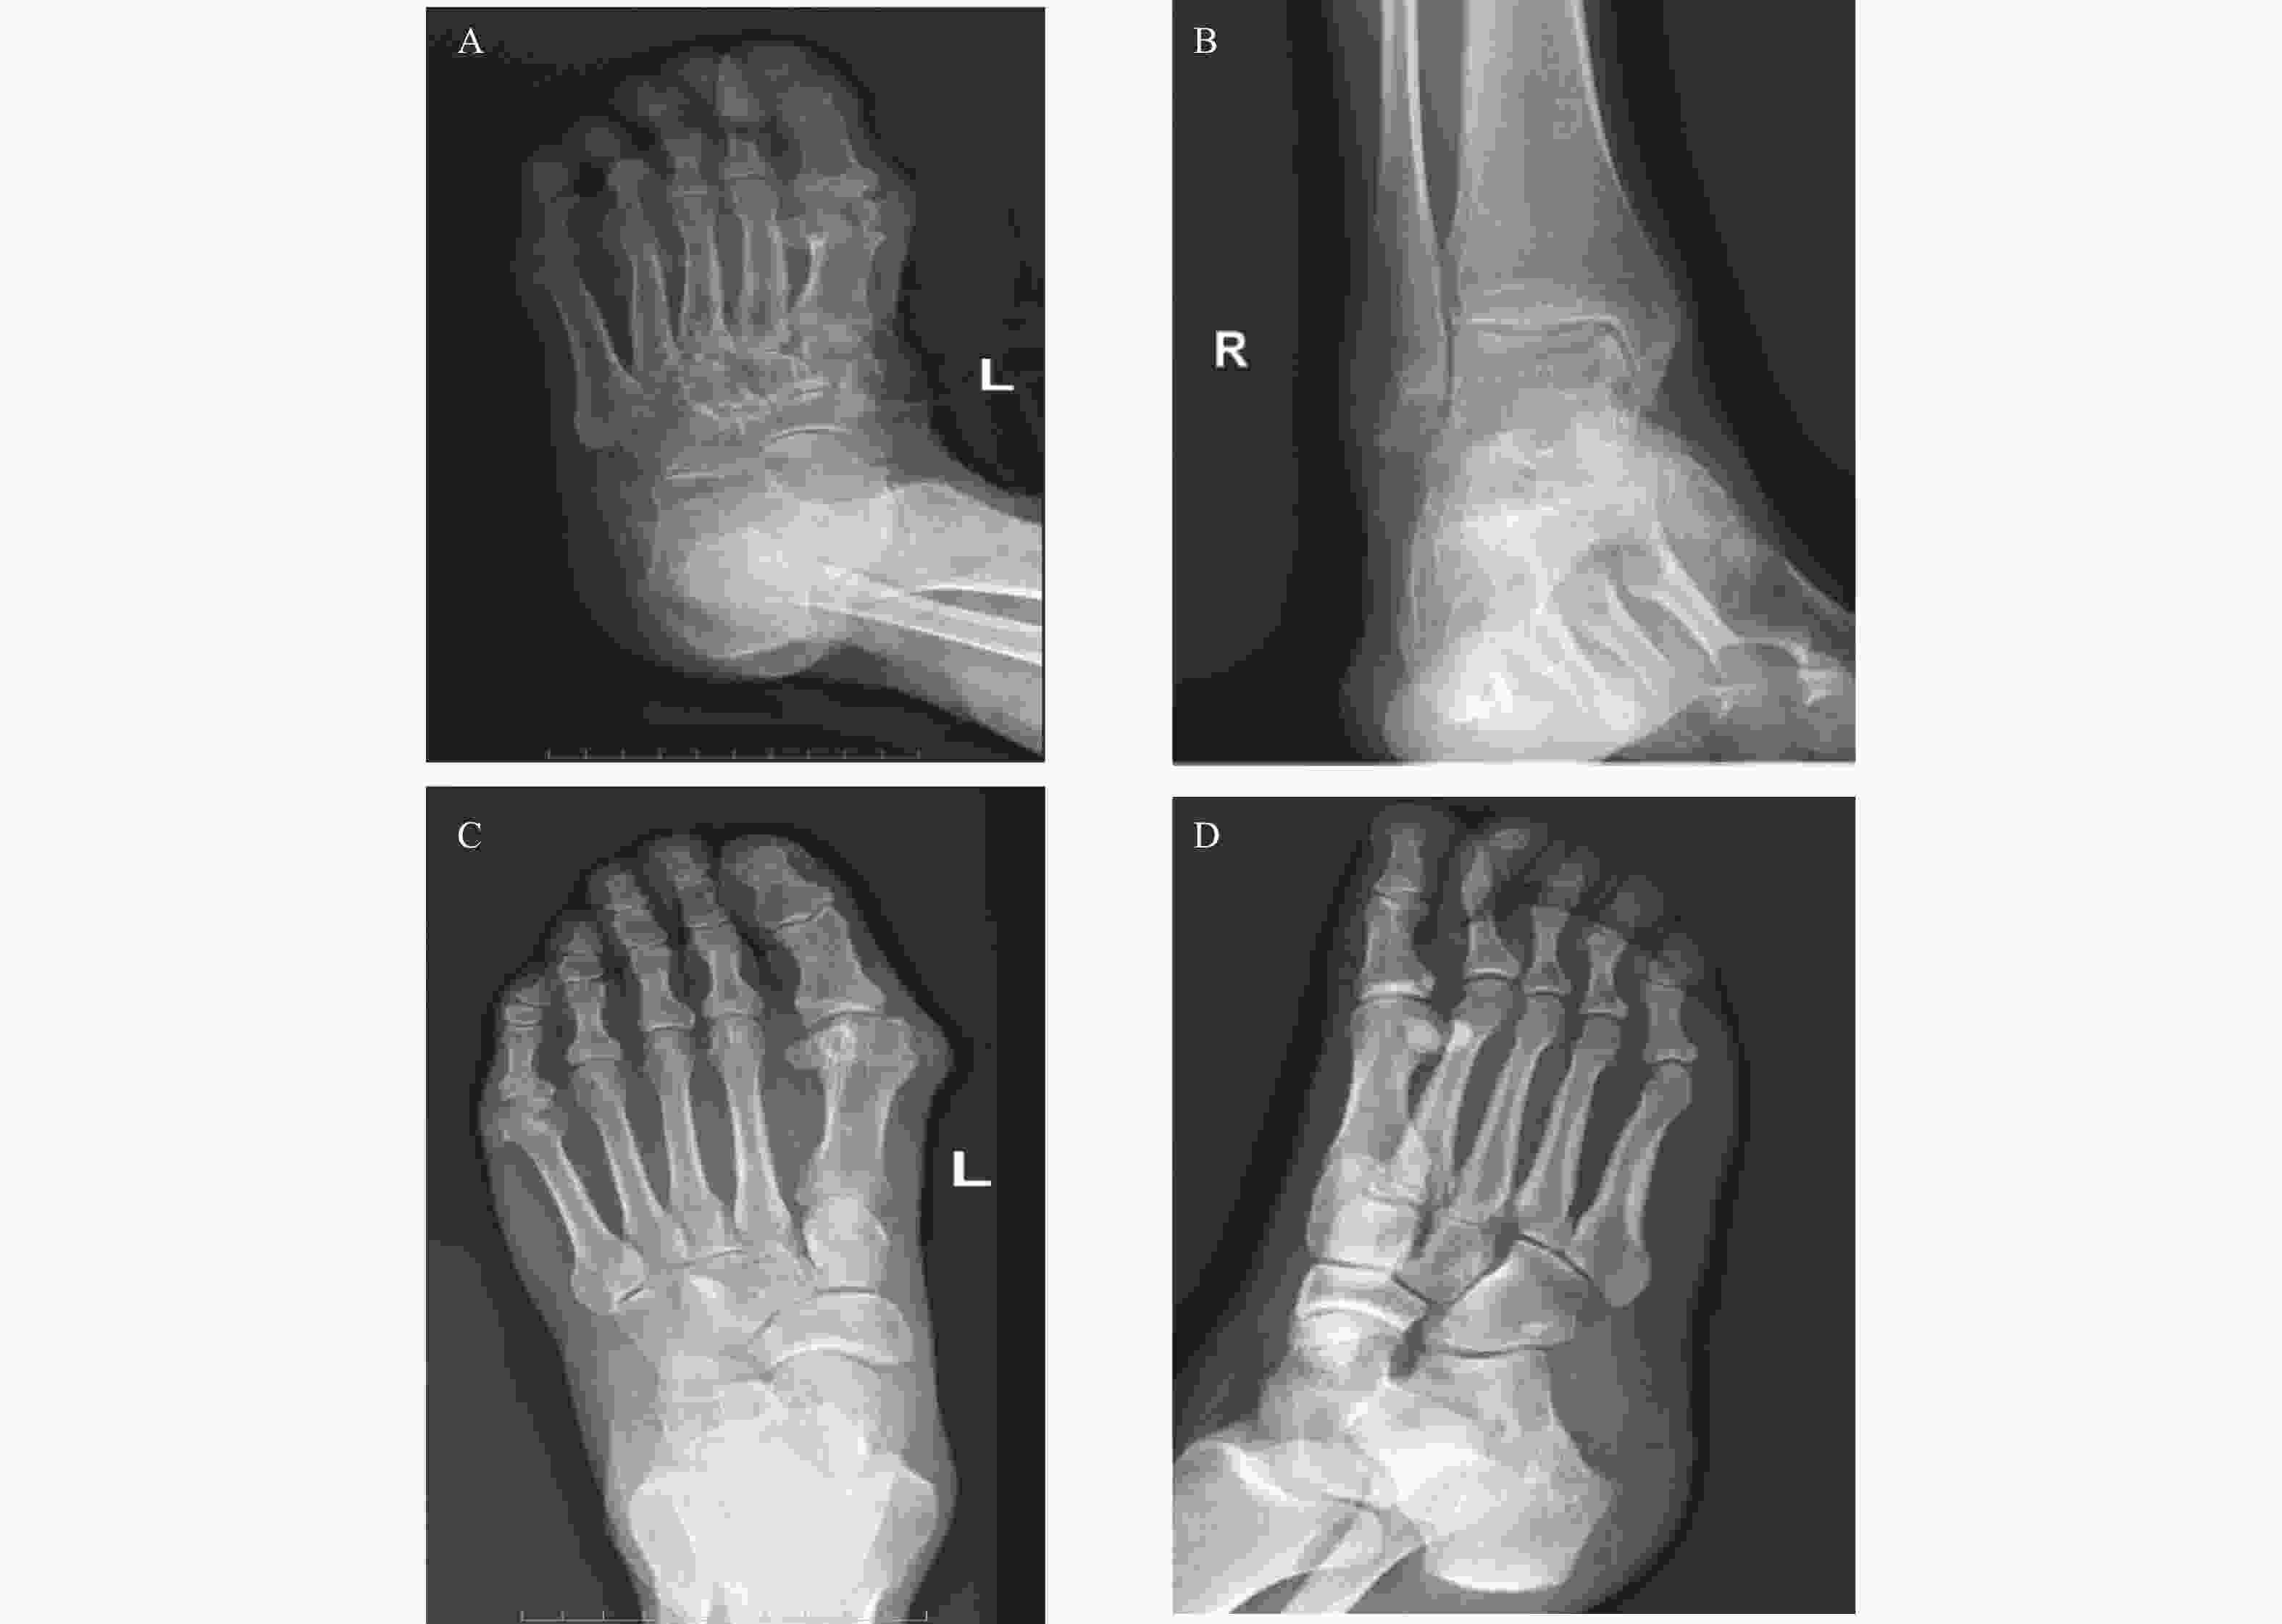

图  3  GA患者与对照组X线图像

A:GA患者左足X线:左足外翻;B:GA患者双踝X线:右踝关节骨质增生;C:GA患者左足X线:第1跖骨骨质欠规整;D:对照组右足X线:未见明显异常。

Figure  3.  X-ray images of GA patients and the control group